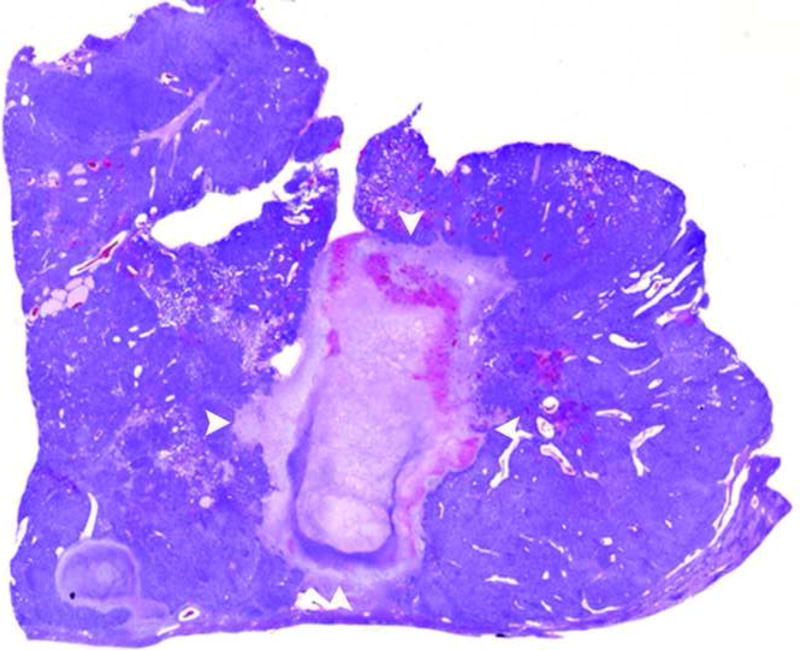

Figure 3.

a and b. Gross (a) and histopathological (b) sections through treated woodchuck liver tumors reveal a central ablation zone within the tumor (arrowheads).

In all 11 woodchucks that underwent MRI after RFA, there was evidence of ablation (Figure 3). Using the modified protocol, the burn areas were consistent, each approximately 1 cm in diameter (mean 10.2mm × 13.1mm, range [7-14]mm × [9-23]mm). Since all HCC treated were larger than 1 cm in diameter, there was evidence of residual tumor in all treated lesions with peripheral nodular enhancement (Figure 4).

All tumors were confirmed to be hepatocellular carcinomas based on typical histological appearance. Viable tumor tissue was readily discerned from treated tissue. Approximately one week following RFA, the treated volume was roughly spherical and showing complete loss of viable tissue and replacement with eosinophilic tissue debris and a circumferential rim of edema and early granulation tissue, characterized by an ingrowth of reactive fibroblasts and small caliber blood vessels. A light infiltration of neutrophils and smaller numbers of lymphocytes was present in the majority of cases. In the two cases that were euthanized or died within a day of RFA, the treated areas consisted of a clearly defined area of coagulative necrosis rimmed with a mild infiltrate of neutrophils.